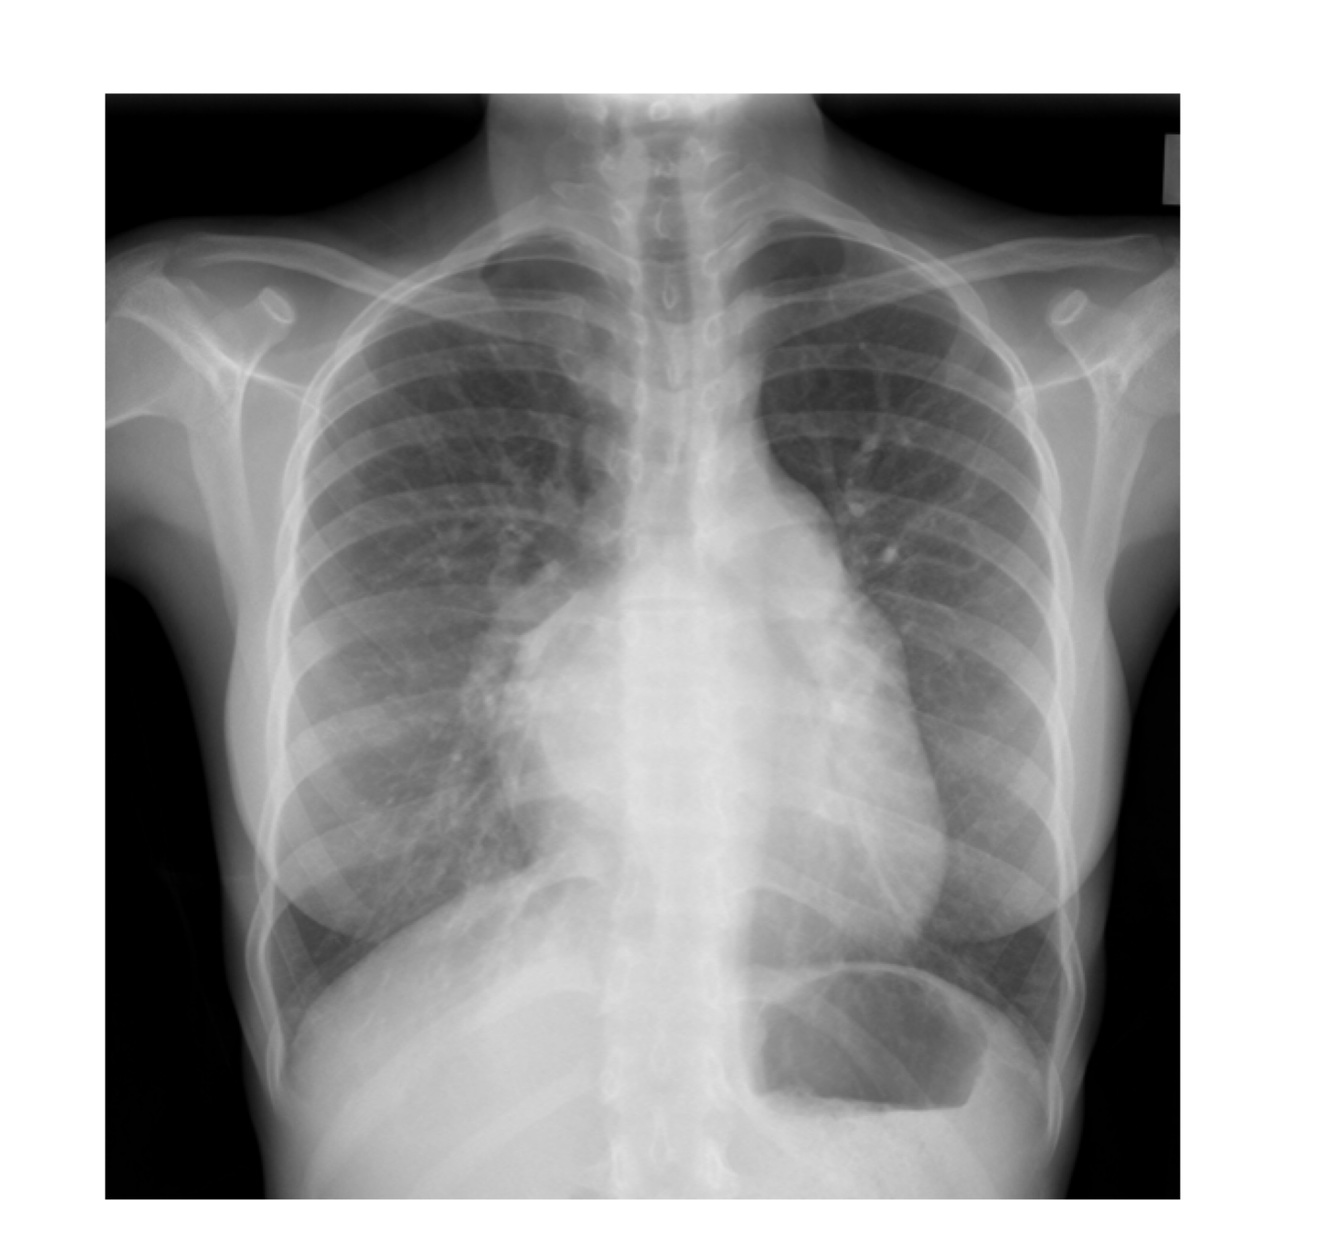

On the CXR left atrial enlargement can be seen. In those with pulmonary hypertension signs of this and right sided heart failure may also feature. The CXR shown below has a number of signs indicative of left atrial enlargement - what murmur is this describing?

On the CXR left atrial enlargement can be seen. In those with pulmonary hypertension signs of this and right sided heart failure may also feature. The CXR shown below has a number of signs indicative of left atrial enlargement: